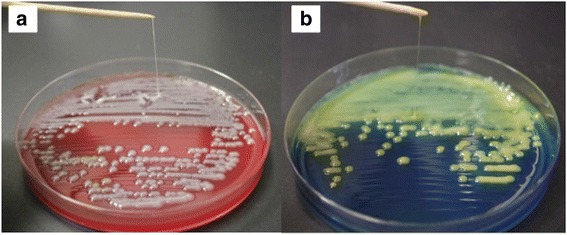

Fig. 2.

String test. Stretching colonies form a string of >5 mm in length in sheep blood agar (a) and in bromothymol blue lactose agar (b)

A 64-year-old woman with an unremarkable medical history was admitted to a nearby hospital for a high fever and diarrhea that had lasted for 1 week. She had vision loss in her right eye, exacerbation of renal dysfunction (serum creatinine level, 4.96 mg/dL), and thrombocytopenia (platelet count, 14,000/μL) within 48 h from initial presentation. Therefore, she was transferred to our institution for treatment of severe infectious disease. On admission, she was alert and had no alteration of mental status, no hypoxia on room air, and normal vital signs (temperature, 36.7 °C; blood pressure, 126/80 mmHg; pulse rate, 74 beats/min; respiratory rate, 12 breaths/min). However, she had almost complete ablepsia of the right eye. Laboratory data showed severe inflammation (white cell count, 21,700/μL; C-reactive protein level, 28.2 mg/dL; procalcitonin, 46.4 ng/mL), liver dysfunction (aspartate transaminase, 147 IU/L; alanine transaminase, 345 IU/L), thrombocytopenia (platelet count, 32,000/μL), an increased serum creatinine level (1.35 mg/dL), and coagulopathy (fibrin/fibrinogen degradation product, 56.6 μg/mL; D-dimer, 24.2 μg/mL; prothrombin time-international normalized ratio, 1.15)(Table 1). Computed tomography showed a low density area in the right lobe of the liver, and she was diagnosed with a liver abscess (Fig. 1a). Broad-spectrum antibiotic therapy with meropenem (3 g/day) was immediately started. Endogenous endophthalmitis of the right eye was also diagnosed, and emergency vitrectomy was performed on the day of admission. The blood culture at admission showed K. pneumoniae, and the antibiotic therapy was changed to ceftriaxone (2 g/day) on day 4 because all of the cephalosporin had high susceptibility (Table 2) and ceftriaxone was known to penetrate to the liver in high concentration, which was continued to day 14. Percutaneous drainage of the liver abscess, which was unresolved by medical treatment, was performed after coagulopathy improved on day 6 (Fig. 1b). The culture of the drainage fluid also showed K. pneumoniae. The drainage tube was removed on day 14, and the patient was discharged in a good general condition on day 22, with an additional 2-week course of oral levofloxacin on days 14–28. However, she had complete ablepsia of the right eye. Capsular probing via PCR for the presence of magA (serotype K1) and K2A (serotype K2) genes was performed by using the magA-specific primers (forward, 5′-GGTGCTCTTTACATCATTGC-3′; and reverse, 5′-GCAATGGCCATTTGCGTTAG-3′) and k2A-specific primers (forward, 5′-CAACCATGGTGGTCGATTAG-3′; and reverse, 5′-TGGTAGCCATATCCCTTTGG-3′) as previously described[7]. The virulence-associated gene rmpA was also screened using PCR by using the rmpA-specific primers (forward, 5′- ACTGGGCTACCTCTGCTTCA-3′; and reverse, 5′- CTTGCATGAGCCATCTTTCA-3′) as previously described [8]. The reaction mixtures of these samples were kept at 95 °C for 5 min, followed by 35 cycles of 95 °C for 1 min, 50 °C for 1 min, and 72 °C for 1 min and then 72 °C for 7 min. The K2A gene, which is consistent with the K2 serotype, was detected by PCR. PCR was also positive for the virulence-associated gene rmpA. To assess for the presence of hypermucoviscosity, a string test was performed on the organism grown in 5 % sheep blood agar. The formation of a mucous string of >5 mm in length after touching a colony with a loop was considered positive [9]. The isolated K. pneumoniae had a positive string test consistent with a hypermucoviscous phenotype (Fig. 2).